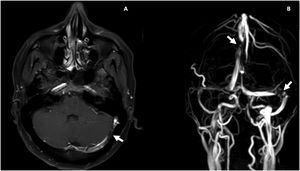

Durante la hospitalización, el día 4 se diagnosticó enteritis lúpica por la presencia de dolor abdominal, diarrea y tomografía de abdomen contrastada con signo de la diana en el íleon distal (fig. 1). Adicionalmente, por episodio de cefalea en trueno (día 7) se realizó angiorresonancia cerebral que detectó trombosis en la confluencia del seno venoso transverso, sigmoideo izquierdo y sagital superior (fig. 2; tabla 1). Por estos hallazgos se inició infusión de inmunoglobulina y anticoagulación.

Resonancia magnética contrastada cerebral. A) T1 posgadolinio, trombosis venosa parcialmente recanalizada en la confluencia del seno trasverso y sigmoideo izquierdo (flecha blanca). B) Venorresonancia, defecto de flujo central en la unión del seno transverso y sigmoideo izquierdo y en el aspecto posterior del seno sagital superior (flechas blancas).